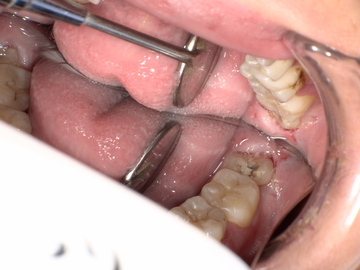

After(下親知らずの抜歯後) 横に生えた状態で埋まっている親知らずの抜歯後 虫歯がある親知らずの抜歯後 抜歯後の骨の状態のレントゲン像

次に局所麻酔を行い、親知らず周囲の歯肉を切開して骨を露出させます。骨の中で横に生えた状態で埋まっている親知らずはそのままでは抜くことができないため、親知らず周囲の骨を一部分削り取り、抜きやすいようにします。

親知らずを複数に分割してから、全て取り除きました。抜歯後は切った歯肉を元の位置に戻し、糸で縫って傷口を閉じます。

1年後、取り除いた親知らず周囲の骨がしっかり再生したことを確認しました。